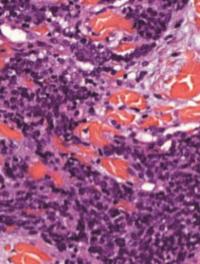

Le papillome inversé est une tumeur bénigne des fosses nasales qui se caractérise par la prolifération de cellules épithéliales en amas (papillome) vers le chorion sous-jacent : cette particularité est à l’origine du vocable inversé. Cliniquement, il entraîne le plus souvent une obstruction nasale unilatérale avec rhinorrhée. Le bilan complémentaire nécessite une IRM centrée sur les cavités sinusiennes et une biopsie. Le traitement est chirurgical et consiste en l’exérèse [...]